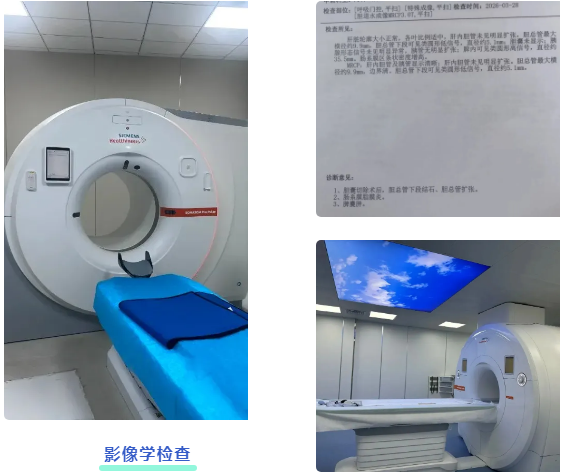

吕后宁主任首先为老人安排了上腹部CT检查。影像结果显示胆总管扩张,其末端可见高密度影,考虑结石可能。结合患者数年前曾有胆囊切除的病史,胆总管末端结石成为首要怀疑诊断。

为进一步明确结石的具体位置、大小,并排除其他可能引起梗阻性黄疸的病因(如胆管肿瘤、胆管狭窄等),随后为患者进行了MRCP检查。这项检查能更清晰地显示胆道系统的全貌。MRCP结果清晰证实了胆总管下端存在充盈缺损,即结石嵌顿,从而明确了胆总管末端结石”的诊断。这一严谨的步骤确保了诊断的准确性,为制定精准的治疗方案奠定了基础。